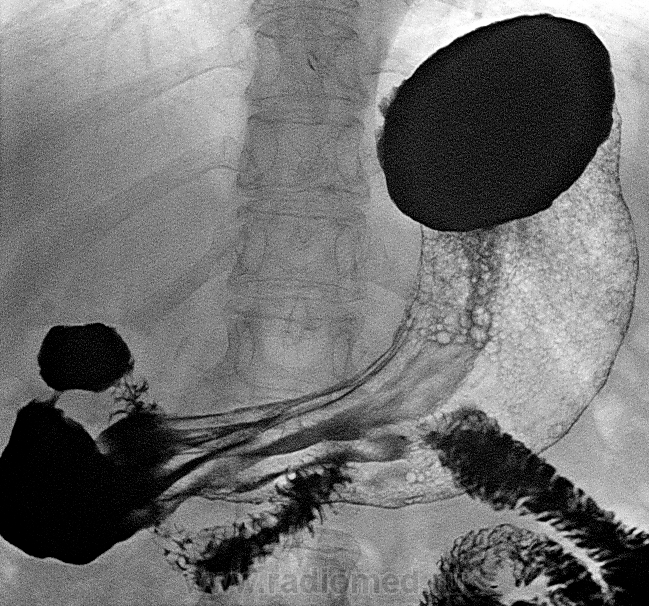

Множественные полипы тела (1 снимок) и антрума (остальные кадры). Утолщены Керкринговы складки в ДПК. Гипотония желудка. Чулок.

Данным случаем решил поделиться, поскольку ни каждый день встречаются множественные полипы антрального отдела желудка, это видно как при компрессии так и при ПДК, кстати единичные полипы тела желудка тоже есть. При ФГДС выявлены гиперпластические полипы слизистой антрального отдела желудка до 8 штук, была взята биопсия(длинные извитые железы, выстланные высоким эпителием, ветвящиеся высокие валики, в строме скудная лимфо-гистиоцитарная инфильтрация)

А я хочу поделиться соображением что мелкая «крупа» в теле желудка, столь хорошо видимая на цифровых снимках, это всё же не воздушные пузырьки а мелкие полипы. Если бы не было крупных можно было бы трактовать их как полипозный гастрит, а в совокупности с крупными – это полипоз желудка. А почему нет? Большие тоже были когда-то маленькими. Эндоскопист про них не пишет – это на его совести. Но у нас ведь свои глаза есть и голова зачем-то…

Ну "полипоз желудка", это наверно громко все же в данном случае будет звучать, что же косается визуализации полипов в теле желудка, единичные видны при тугом наполнении на 1ом снимке, следующие три снимка там уже шипучка и интерпритация данной картины как "множественые полипы" это будет ошибочно, в дальнейшем при смене положения тела они же куда то деваются, рельеф слизистой прослеживается, так что "множественные полипы" все же будет применим к антральному отделу желудка.

ИХ видно на всех снимках лёжа, где есть тело желудка и воздух в нём. ИХ не видно стоя, так ведь и больших стоя не видно!

ВИДНЫ ОНИ И НА ПЕРВОМ СНИМКЕ.

БЕЗ ШИПУЧКИ.